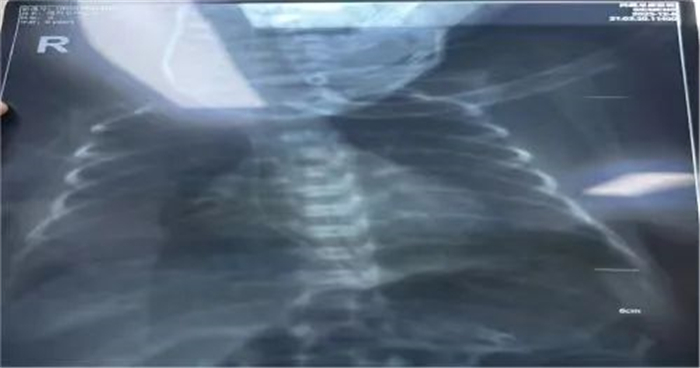

接到護理會診通知后,我院靜療團隊(IVTEAM)高度重視,認真評估患兒情況,來到科室映入眼簾的是溫箱里四肢僅有拇指粗細,血管更是細如發(fā)絲的早產(chǎn)寶寶,了解到普通留置針穿刺實屬不易,但置入PICC更是難上加難,對于我們靜療團隊來說是無疑是一個巨大的挑戰(zhàn)。在ICU任周行護士長的指導(dǎo)下,靜療學組組長韓曉倩、鄧倩雯準備好物品,代金麗護士長小心翼翼地為寶寶擺好體位,大家一起做好基本生命支持及保暖工作,充分評估血管情況后,組長韓曉倩最終選擇經(jīng)右上肢貴要靜脈進針,憑借過硬的穿刺技術(shù),穿刺時一針見血,隨后送管、撤導(dǎo)絲、固定一氣呵成,經(jīng)X線定位確定 PICC 導(dǎo)管尖端位置良好,成功了,大家終于松了一口氣!